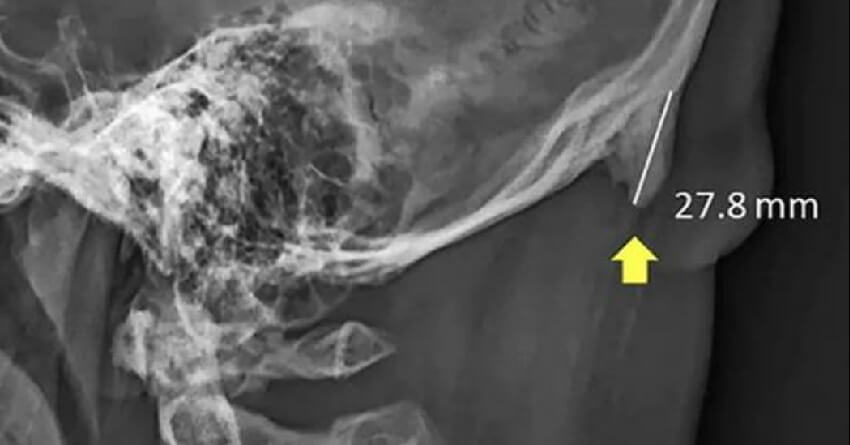

ક્વીન્સલેન્ડમાં લેવામાં આવેલા ગરદન એક્સ-રેના રિપોર્ટ સાથે ત્રણ વર્ષ પહેલાં તેમનું રિસર્ચનું કાર્ય શરૂ થયું હતું. ખોપરીના આ એક્સ-રેમાં સ્પષ્ટ દેખાતું હતું કે આ વિસ્તારનું એક હાડકું જરૂર કરતાં વધેલું હતું. તેને તબીબી ભાષામાં એન્થોસોફિટ્સ કહેવાય છે, જે માથાના પાછળના ભાગમાં જોવા મળે છે.

સંશોધકોનું પ્રથમ પેપર વર્ષ 2016માં જર્નલ ઓફ એનાટોમીમાં પ્રકાશિત થયું હતું, જેમાં 18 થી 30 વર્ષની વયના 218 યુવાનોના ખોપરીના એક્સ-રે લેવામાં આવ્યા. જેમાં 41% યુવાનોની ખોપરીમાં હાડકાંનો આ વધેલો ભાગ જોવા મળ્યો. મહિલાઓની સરખામણીએ પુરુષોમાં આ ભાગ વધુ જોવા મળ્યો. વર્ષ 2018માં ક્લિનિકલ બાયોમિકેનિક્સ જર્નલમાં પ્રકાશિત થયેલા અન્ય એક પેપરમાં ચાર ટીનેજર્સનો સમાવેશ કરવામાં આવ્યો હતો. જેમાં ખોપરીમાં વધેલું આ શિંગડાથી ગળાના સ્નાયુઓને ભાર પડે છે એ વાત કરવાને બદલે એવી દલીલ કરવામાં આવી હતી કે માથાના ઊગતું આ શિંગડાનું કારણ આનુવંશિક પરિબળો કે બળતરા નથી.

આખરે મહિના અગાઉ પ્રકાશિત થયેલા ક્વિન્સલેન્ડના સાયન્ટિફિક રિપોર્ટ્સમાં 18 થી 86 વર્ષની વયના 1,200 એક્સ-રેના નમૂનાને ધ્યાનમાં લેવામાં આવ્યા. જેમાં સંશોધકોએ શોધી કાઢ્યું હતું કે વસ્તીના 33% લોકોમાં હાડકાંના વિકાસનું કદ ઉંમર સાથે ઘટતું ગયું હતું. આ શોધ અસ્તિત્વમાં રહેલી વૈજ્ઞાનિક સમજણથી વિપરીત હતી, જેણે લાંબા સમય સુધી એવું માન્યું હતું કે ખોપરીનું આ શિંગડાવાળું હાડકું ઉંમર વધવાની સાથે વધે છે. આ ઉપરાંત, જો બાળપણમાં વધુ સ્ટ્રેસ પડ્યો હોય તો પણ આ હાડકું વધી શકે છે એવું પણ તારણ નીકળ્યું.